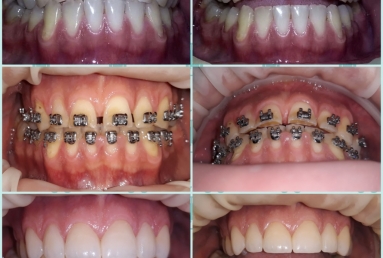

This patient has advanced dental abrasion due to bruxism ( clenching the teeth during the night). this is why the bite is modified and the frontal teeth are shorter. First stage of the treatment is wearing a night guard to relax the muscles and the temporo-mandibular jaw.

Then fixed orthodontic treatment is set for almost 2 years, so moving the teeth a new more favorable position is obtained to create space for veneers. After wax up a mock up is done for provisional veneers and the new occlusion is tested.